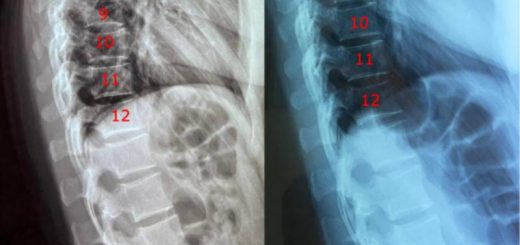

Reversal of L5 and L4 Disc Degeneration